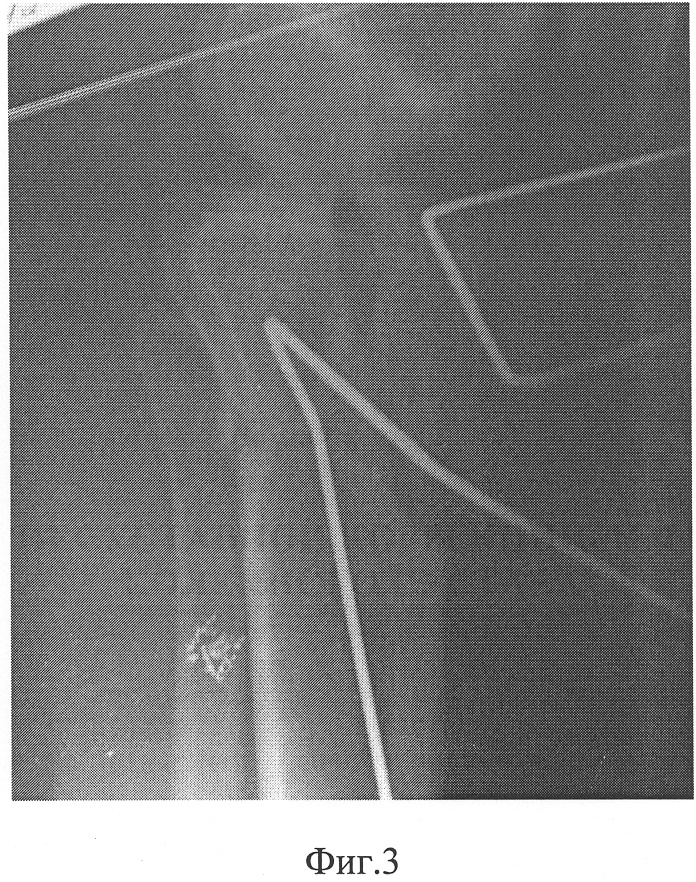

Фиг.1 – боковая проекция (вид сбоку) до лечения;

В СарНИИТО больной было проведено обследование. На рентгенограмме левой конечности в боковой проекции (фиг.1) зафиксировано переразгибание коленного сустава со смещением в сагиттальной плоскости мыщелка голени кзади на 8 мм, что свидетельствует о подвывихе и рекурвации.